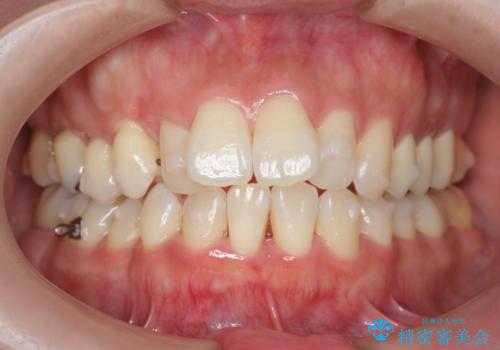

職業柄ワイヤー矯正ができない、マウスピース矯正で行う八重歯抜歯症例

- 2年6ヶ月

通常は八重歯の抜去は行わず、小臼歯の抜去を行いワイヤー矯正を行いますが、八重歯を抜去することでマウスピースで現実的に達成できる機能的な歯並びを獲得できるよう治療計画を立案します。